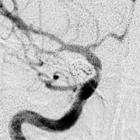

3.脑血管造影是确诊颅内动脉瘤必须的检查方法,对判明动脉瘤的准确位置、形态、内径、数目、血管痉挛和确定手术方案都十分重要。DSA更为清晰。,经股动脉插管全脑血管造影,可避免遗漏多发动脉瘤。病情在三级以下,脑血管造影应及早进行,三级和三级以上病人可待病情稳定后,再行造影检查。及早造影明确诊断,尽快手术夹闭动脉瘤,可以防止动脉瘤再次破裂出血。首次造影阴性,可能因脑血管痉挛而动脉瘤未显影,高度怀疑动脉瘤者,应在3个月后重复造影。